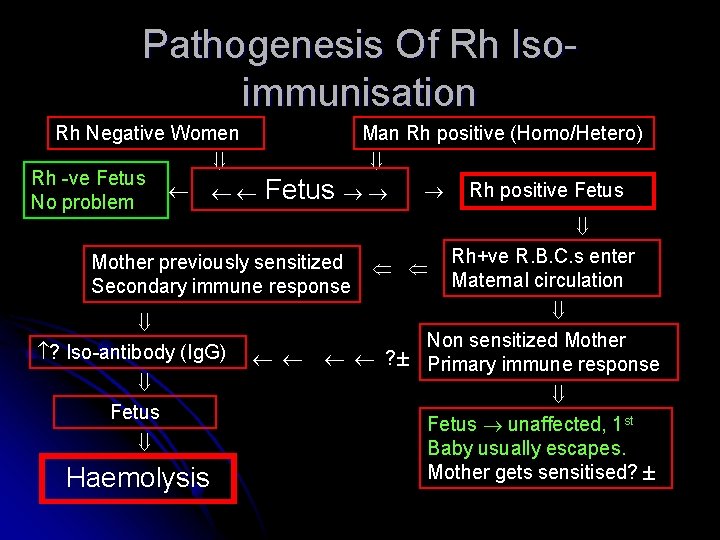

Pathogenesis Of Rh Isoimmunisation Rh Negative Women Rh -ve Fetus No problem Man Rh positive (Homo/Hetero) Fetus Mother previously sensitized Secondary immune response ? Iso-antibody (Ig. G) Fetus Haemolysis Rh positive Fetus Rh+ve R. B. C. s enter Maternal circulation Non sensitized Mother ? Primary immune response Fetus unaffected, 1 st Baby usually escapes. Mother gets sensitised?